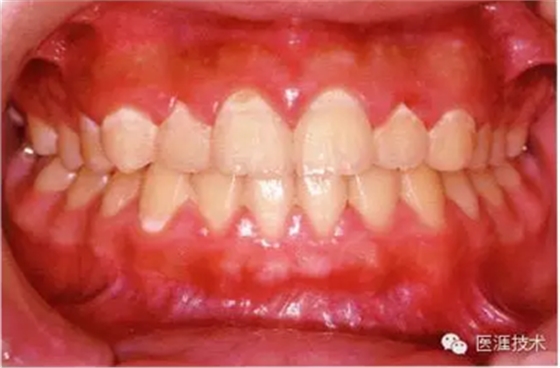

18歲男性的健康口腔內(nèi)部

圖為18歲男性,無特殊全身疾病,不抽煙。持續(xù)保養(yǎng)10年。牙菌斑控制比以前好,因刷牙稍稍過度臉頰側(cè)有牙齦萎縮傾向,但牙齒及牙周組織仍保健康。